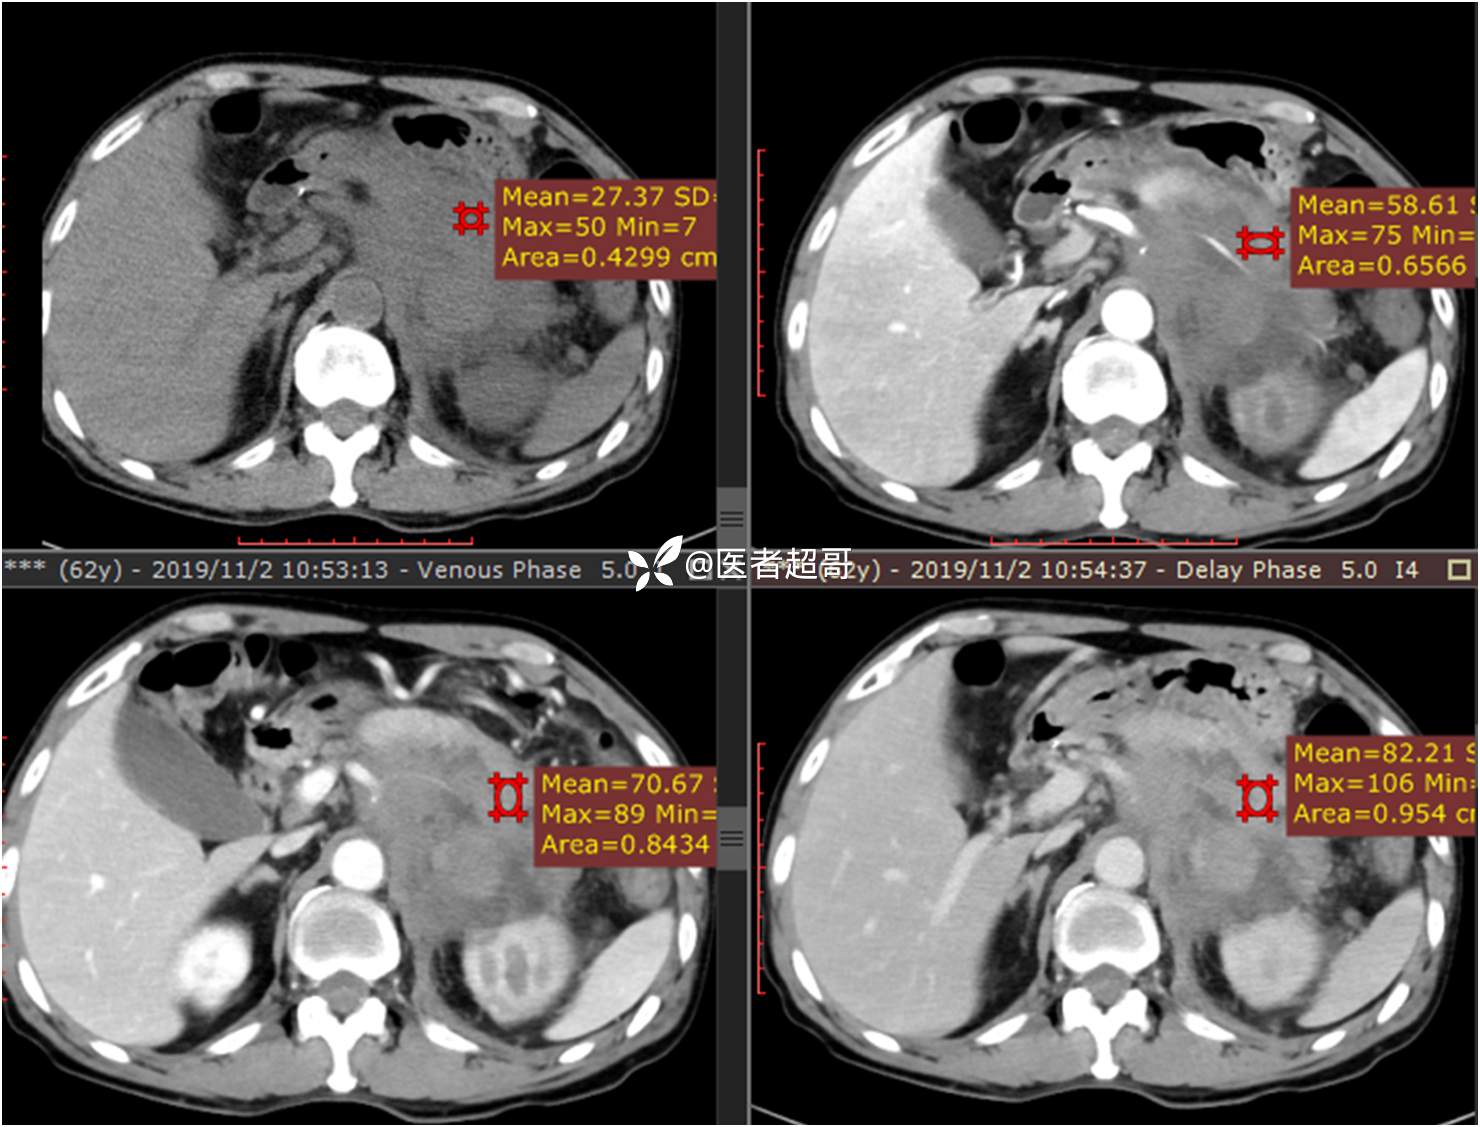

现病史:患者于1月前无明显原因及诱因出现左上腹部疼痛,为间断性疼痛,无恶心、呕吐,无寒战、高热,无腹胀、腹泻等伴随症状,在外未行特殊处理,患者于1周前自觉疼痛加重,为求诊治患者曾就诊于市东城医院,行全腹部强化CT提示:左肾上腺区肿块,符合恶性肿瘤侵犯左肾、胰腺及腹膜后大血管CT表现,行保守治疗,症状缓解,今患者为求进一步诊治,来我院就诊,行腹膜后占位穿刺活检病理提示:(腹膜后占位穿刺)小细胞背景内见细胞浆红染的神经节样细胞,建议到病理科加做免疫组化进一步明确诊断,遂以“腹膜后肿物”收入院,患者自发病以来,神志清,精神可,饮食、睡眠差,大小便正常,体重未见明显改变。